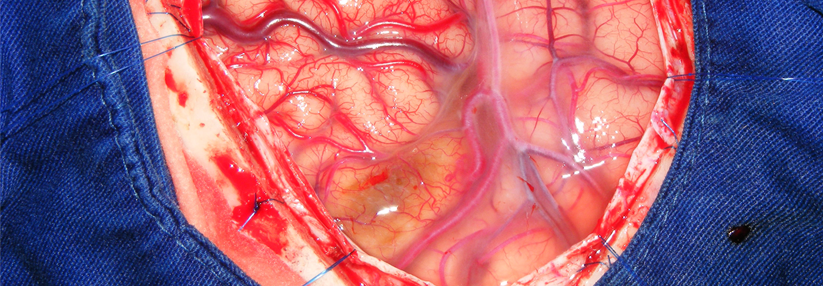

Invasive und Interventionelle Therapie

Ausschaltung des Aneurysmas

• falls Ausschaltung indiziert und möglich, sollte sie innerhalb der ersten 72 Stunden erfolgen (vor Auftreten der Vasospasmen)

• endovaskuläres Coiling oder chirurgisches Clipping (Entscheidung im interdisziplinären Team), bei Machbarkeit Coiling bevorzugen (wegen besserer Langzeitergebnisse)